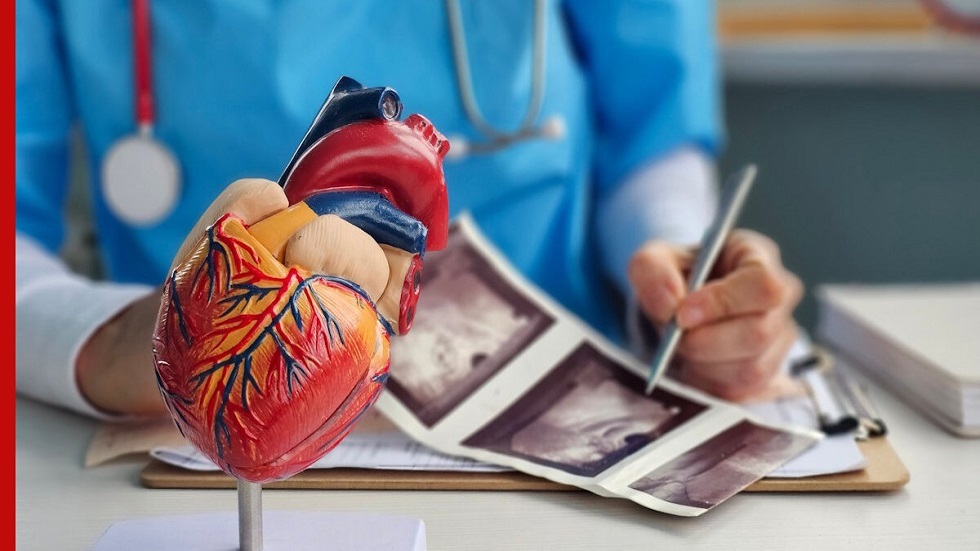

تقنية نانوية روسية تشخص النوبة القلبية خلال 6 دقائق فقط

طوّر باحثون من روسيا جيلا جديدا من الاختبارات السريعة لتشخيص احتشاء عضلة القلب (النوبة القلبية)، وبإمكان هذا الاختبار اكتشاف المرض في ست دقائق فقط.

ومع ذلك، تفوق حساسية الاختبار الجديد نظائره الحالية بنحو 45 ضعفا، وفقا لما أفادت به وكالة "تاس" نقلا عن الخدمة الصحفية لمعهد موسكو للفيزياء والتقنيات.

وقال كبير الباحثين في معهد الفيزياء العامة التابع لأكاديمية العلوم الروسية، أليكسي أورلوف:

"لطالما واجهت الاختبارات السريعة معادلة صعبة: إما السرعة والبساطة، أو الدقة. لكننا تمكّنا من تجاوز هذه المفاضلة جذريا، إذ لم نعمل على تحسين العلامات التقليدية فحسب، بل استبدلناها بسلاسل نانوية تنشط داخل مجال مغناطيسي دوّار".

وأوضح أورلوف وزملاؤه أن سرعة تشخيص احتشاء عضلة القلب تؤثر بشكل مباشر في فرص نجاة المريض، إلا أن الطرق المخبرية الحالية تستغرق ما بين 30 و60 دقيقة، وتتطلب معدات خاصة وكوادر مؤهلة. كما أن الاختبارات السريعة المتاحة غالبا ما تعطي نتائج سلبية كاذبة بسبب انخفاض حساسيتها، ما يحدّ من فعاليتها.

وتمكّن العلماء الروس من تحقيق تقدم مهم عبر دمج مستشعرات تعتمد على سلاسل نانوية ضمن نظام الاختبار السريع. وتتكوّن هذه السلاسل من خيوط من جسيمات أكسيد الحديد النانوية بطول يقارب ميكرومترا واحدا، وترتبط بها أجسام مضادة قادرة على التعرف على بروتين H-FABP، وهو أحد المؤشرات الحيوية لاحتشاء عضلة القلب. ويظهر هذا البروتين في مجرى الدم خلال الساعة الأولى من بداية النوبة، ما يتيح تشخيص الحالة بسرعة عالية.

وتكمن الميزة الأساسية لهذه الهياكل النانوية في قدرتها على تحريك الدم المحيط بها عند تعرّضها لمجال مغناطيسي دوّار، ما يسرّع تفاعل بروتين H-FABP مع الأجسام المضادة بعشرات المرات. وخلال الاختبار، تبدأ السلاسل النانوية المرتبطة بالمؤشر الحيوي في التجمّع، ما يعزّز الإشارة ويقلّل الضوضاء الخلفية بنحو النصف.

ووفقا للباحثين، لا يتطلب نظام الكشف الجديد تعديل شرائط الاختبار التقليدية، التي تظل منخفضة التكلفة وسهلة التصنيع، كما يحتاج فقط إلى مولّد بسيط لمجال مغناطيسي دوّار يعمل ببطاريات عادية. ومن المتوقع أن يتيح ذلك مستقبلا تطوير اختبارات رخيصة وموثوقة قادرة على الكشف عن عدة مؤشرات حيوية لتلف القلب باستخدام قطرة دم واحدة.